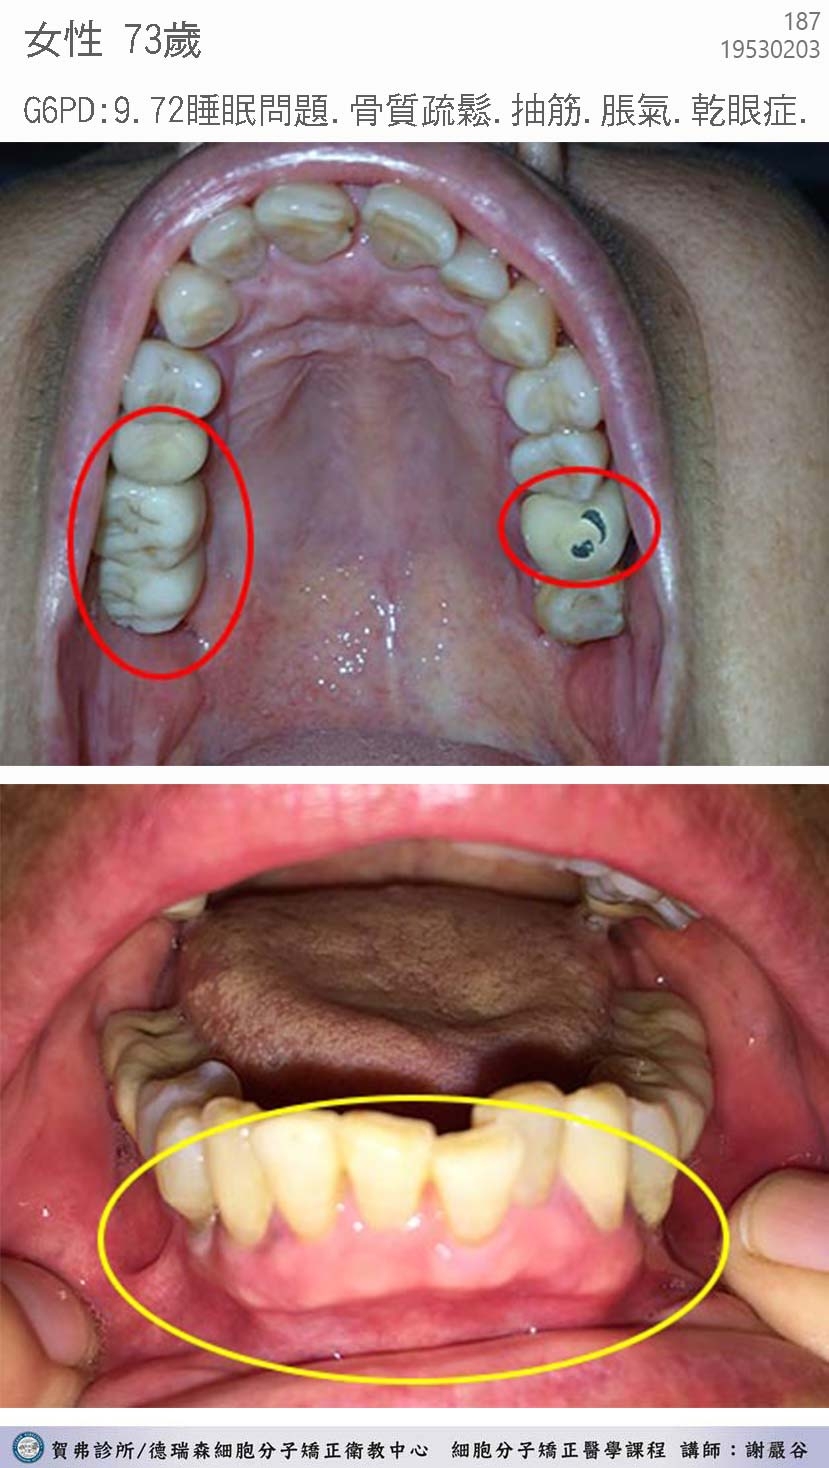

典型汞中毒症候群個案 hgscs0001